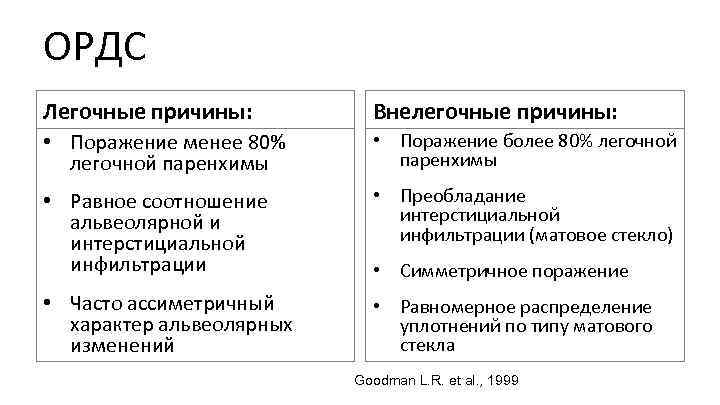

ОРДС Легочные причины: Внелегочные причины: • Поражение менее 80% легочной паренхимы • Поражение более 80% легочной паренхимы • Равное соотношение альвеолярной и интерстициальной инфильтрации • Преобладание интерстициальной инфильтрации (матовое стекло) • Часто ассиметричный характер альвеолярных изменений • Равномерное распределение уплотнений по типу матового стекла • Симметричное поражение Goodman L. R. et al. , 1999